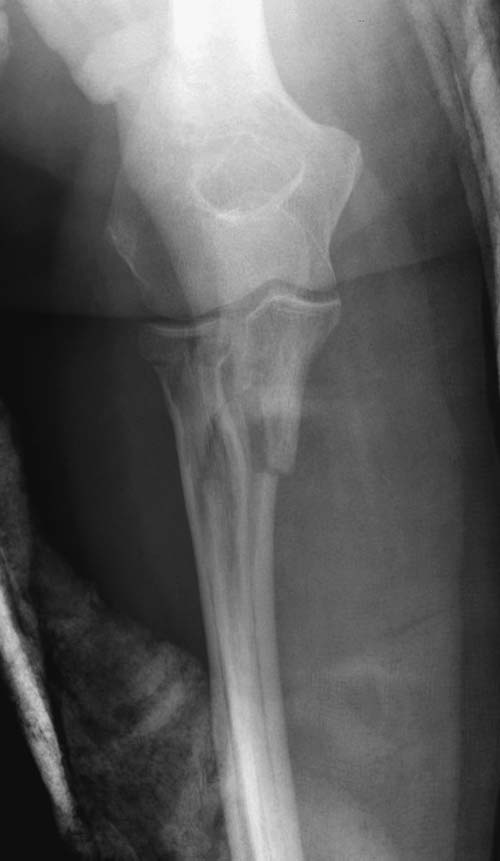

Здесь представлены несколько случаев и как видно больше больных с

серьезными повреждениями, чем изолированные..

В первом случае перелом Монтеджи, где доперационно сделано оценка

положения головки к остальным элементам под рентгеном. Учитывая

правильность взаимотношении произведена фиксация только локтевого

отростка, Второй случай, заменена на протез, и третий, кроме фиксации

головки - реконструкция capitellum латерального мыщелка.

Вложение не в текстовом формате было извлечено…

Имя     : 4 Radial head olecranon.jpg

Тип     : image/jpeg

Размер  : 37190 байтов

Описание: отсутствует

Url     : http://weborto.net:8080/pipermail/ortho/attachments/20131119/c3543de4/attachment-0010.jpg